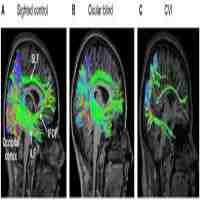

| Abstract | Cortical (cerebral) visual impairment (CVI) results from perinatal injury to visual processing structures and pathways of the brain and is the most common cause of severe visual impairment or blindness in children in developed countries. Children with CVI display a wide range of visual deficits including decreased visual acuity, impaired visual field function, as well as impairments in higher-order visual processing and attention. Together, these visual impairments can dramatically influence a child's development and well-being. Given the complex neurologic underpinnings of this condition, CVI is often undiagnosed by eye care practitioners. Furthermore, the neurophysiological basis of CVI in relation to observed visual processing deficits remains poorly understood. Here, we present some of the challenges associated with the clinical assessment and management of individuals with CVI. We discuss how advances in brain imaging are likely to help uncover the underlying neurophysiology of this condition. In particular, we demonstrate how structural and functional neuroimaging approaches can help gain insight into abnormalities of white matter connectivity and cortical activation patterns, respectively. Establishing a connection between how changes within the brain relate to visual impairments in CVI will be important for developing effective rehabilitative and education strategies for individuals living with this condition. |